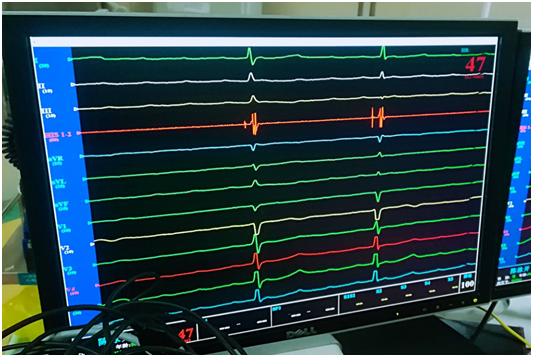

術(shù)中His電位

反復(fù)多次嘗試,歷經(jīng)各種挑戰(zhàn),制定相應(yīng)對(duì)策,終于柳暗花明!電極與his點(diǎn)位緊密結(jié)合成革命伉儷,測(cè)試起搏閾值為0.4V,阻抗為460Ω,起搏心電圖如同正常心電圖,參數(shù)非常理想,甚至是超出預(yù)期的理想。

術(shù)后起搏心電圖